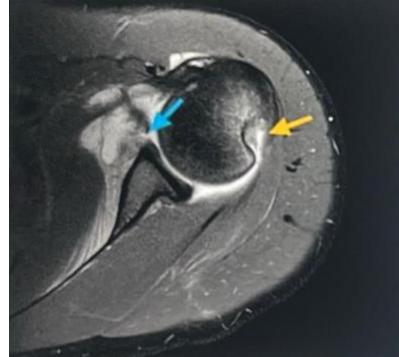

Case: Adhesive Capsulitis (Frozen Shoulder)

Clinical Scenario

- Patient: 55-year-old male, diabetic

- Complaint: Pain and restriction of shoulder movement

Physical Examination Findings:

Assessment Questions

Q1: Describe the physical finding?

- The patient is unable to raise his right hand above his head

Q2: What is your differential diagnosis?

- Adhesive capsulitis (Frozen Shoulder) - Primary diagnosis

- Acromioclavicular arthritis

Q3: What is the treatment for such a case?

- Steroid injection

- Physiotherapy

- Arthroscopic release